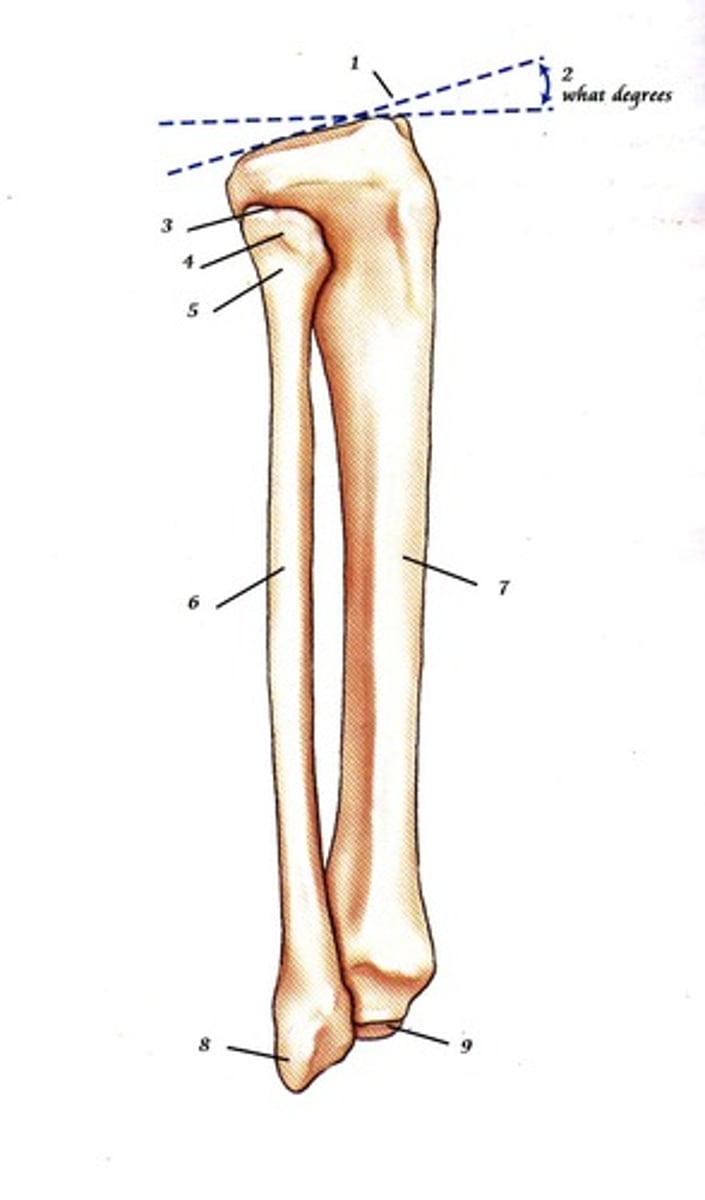

1

10-20

2- what degree angle

apex of fibula

3

head of fibula

4

neck of fibula

5

body of fibula

6

body of tibia

7

lateral malleolus

8

medial malleolus

9